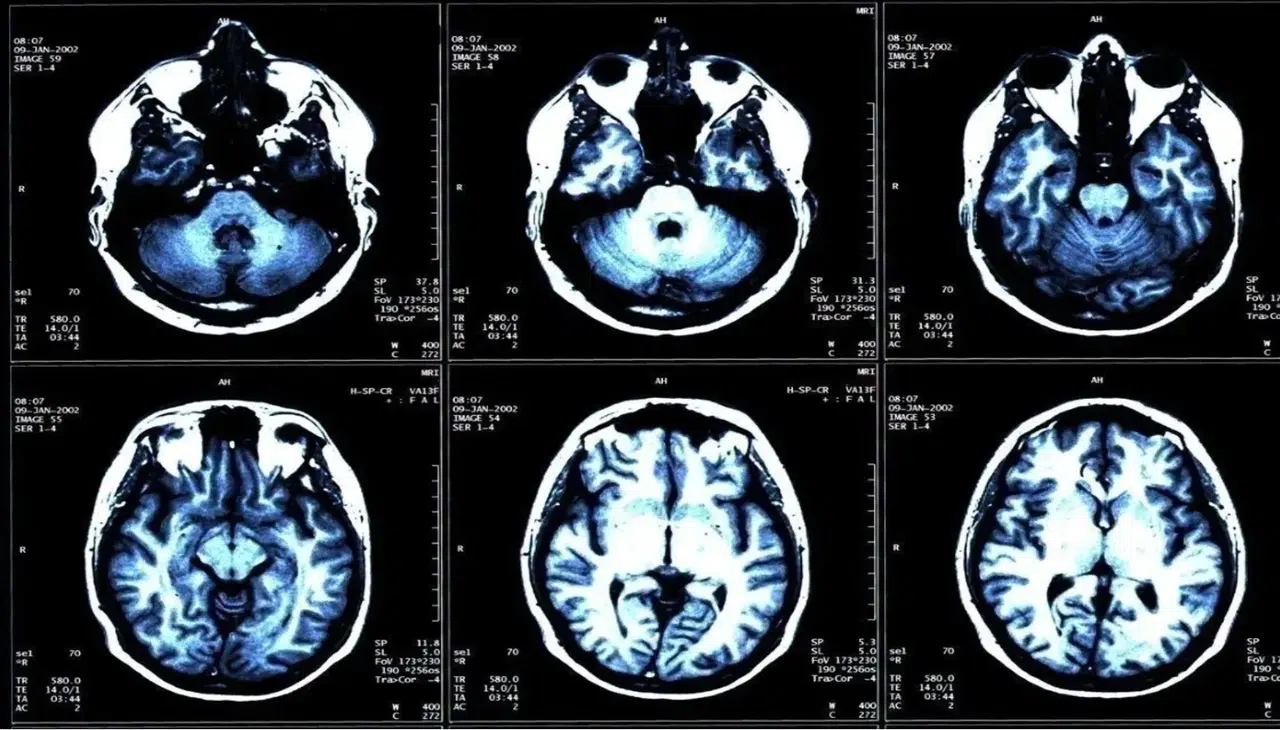

İyot, insan vücudunun sağlıklı işleyişi için hayati önem taşıyan elementlerden biri olarak biliniyor. Tiroid hormonlarının üretiminde temel rol oynayan bu madde, özellikle çocukların büyüme süreci ve beyin gelişimi açısından büyük önem taşıyor. Uzmanlara göre, iyot eksikliği yalnızca fiziksel gelişimi değil, aynı zamanda zihinsel performansı da doğrudan etkiliyor. 21 Ekim Küresel İyot Eksikliği Bozukluklarını Önleme Günü kapsamında açıklamalarda bulunan Endokrinoloji ve Metabolizma Hastalıkları Uzmanı Prof. Dr. Mehmet Fatih Kılıçlı, “Toplumda yeterli iyot alımı sağlıklı nesillerin yetişmesi için kritik bir gerekliliktir” diyerek önemli bir uyarıda bulundu.

Dünya genelinde önlenebilir zeka geriliğinin en sık nedenlerinden biri olarak kabul edilen iyot eksikliği, gelişmekte olan ülkelerde ciddi bir halk sağlığı sorunu olarak görülüyor. Uzmanlara göre bu durum, özellikle kırsal bölgelerde ve iyotlu tuz kullanımının yeterli olmadığı toplumlarda daha yaygın şekilde görülüyor.

Prof. Dr. Kılıçlı’ya göre iyot eksikliği, en çok gebelik döneminde tehlike yaratıyor. Anne adaylarının yeterli iyot alamaması durumunda bebekte kalıcı zeka geriliği, gelişim bozuklukları, ölü doğum ve düşük riski ortaya çıkabiliyor. Ayrıca doğum sonrası dönemde de bebeklerde guatr ve tiroid hormon eksiklikleri gözlenebiliyor. Uzmanlar, gebelik süresince iyot alımının düzenli takip edilmesi gerektiğini, bu dönemdeki eksikliğin hem annenin hem de bebeğin yaşam boyu sağlığını etkileyebileceğini belirtiyor.

Büyüme çağındaki çocuklarda da benzer şekilde iyot yetersizliği gelişim geriliğine, dikkat eksikliğine ve öğrenme güçlüğüne neden olabiliyor. Yetişkinlerde ise uzun süreli eksiklik tiroid bezinde büyümeye, nodül oluşumuna ve kalıcı guatr gelişimine yol açabiliyor.